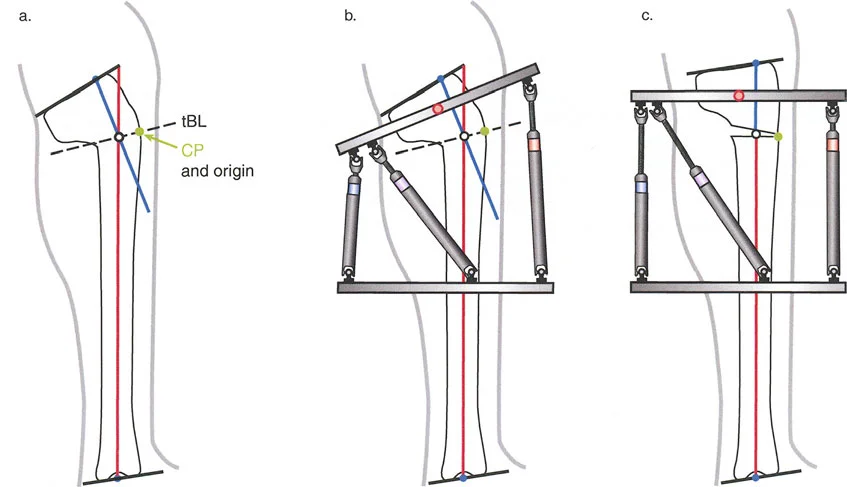

المفصلات القريبة من المفصل وقواعد قطع العظم (Osteotomy Rules)

عند التعامل مع التشوهات الواقعة بالقرب من خط المفصل - مثل التقوس الشديد في الجزء العلوي من الساق (مرض بلونت) أو التشوه الفحجي في الجزء السفلي من عظم الفخذ - يصبح وضع الجهاز مقيدًا هندسيًا. إن المتطلبات البيولوجية للحفاظ على كبسولة المفصل، وتجنب وضع الأسلاك داخل المفصل، ومنع التهاب المفاصل القيحي، غالبًا ما تجبر الجراح على وضع الحلقة المرجعية على مستوى مختلف تمامًا عن مركز دوران الانحراف (CORA) الفعلي.

تحدي مركز دوران الانحراف (CORA) القريب من المفصل

لمطابقة مفصلة المثبت الخارجي مع المستوى الدقيق لمركز دوران الانحراف (CORA)، يجب غالبًا بناء المفصلة فوق أو تحت مستوى الحلقة الفعلية. يُعرف هذا في مبادئ بالي باسم تجميع المفصلة القريبة من المفصل (juxta-articular hinge assembly).

إذا كان مركز دوران الانحراف (CORA) يقع بالقرب من خط المفصل، فإن وضع حلقة إليزاروف القياسية عند هذا المستوى بالضبط مستحيل دون انتهاك مساحة المفصل أو شد الهياكل الكبسولية الحيوية. لذلك، يتم تثبيت الحلقة المرجعية بالعظم الكثيف أو العظم الطويل المتاح، ويتم بناء آلية المفصلة باستخدام قضبان ملولبة، ولوحات توصيل، ودعامات. ثم يتم "إنزالها" (أو رفعها) لتتطابق تمامًا مع مركز دوران الانحراف (CORA) الهندسي الحقيقي.

في المنشآت القريبة من المفصل، غالبًا ما نعتمد على قاعدة قطع العظم 2. نظرًا لأنه لا يمكننا قطع العظم بأمان عند خط المفصل تمامًا (مركز دوران الانحراف CORA)، فإننا نقطع العظم في مستوى أدنى في منطقة الميتافيسيس. بعد تحقيق التصحيح الزاوي عبر المفصلات (محور تصحيح الانحراف ACA)، يتم إعادة محاذاة خطوط المحور الميكانيكي بشكل مثالي، ولكن نهايات العظم في موقع قطع العظم تتحرك بالنسبة لبعضها البعض.